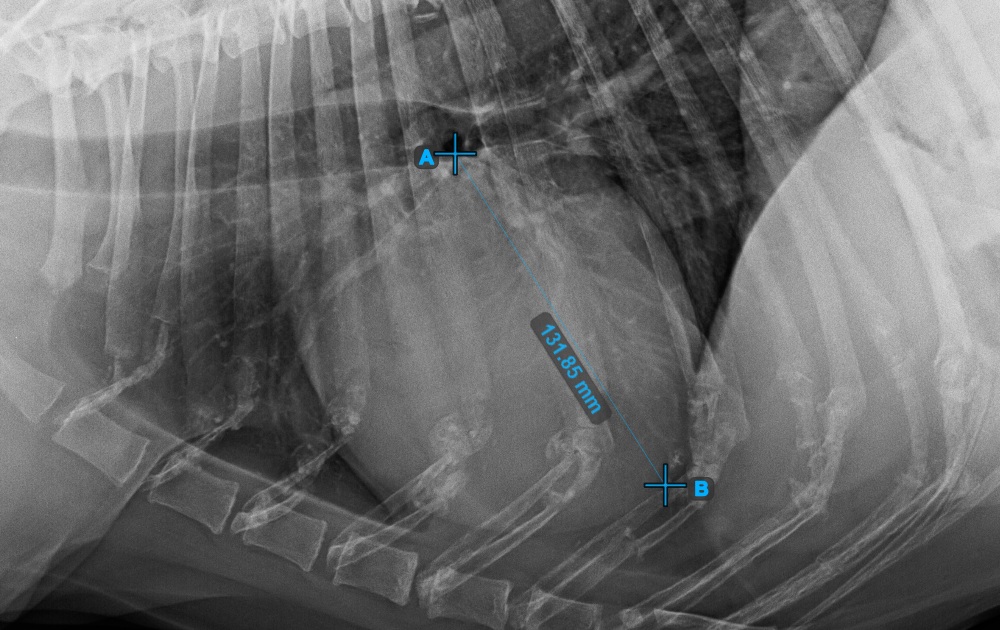

Fejezze be a szív hosszanti tengelyét az Apex pont megjelölésével, a szív alsó részéhez közel.

Az alábbi kép az Apex pont tipikus elhelyezkedését mutatja.

Folytassa a mérést a szív rövid tengelyének legszélesebb jobb (feji) pontjának megjelölésével.

Az alábbi kép a szív rövid tengelyének „legcranialisabb” pontjának tipikus elhelyezkedését szemlélteti